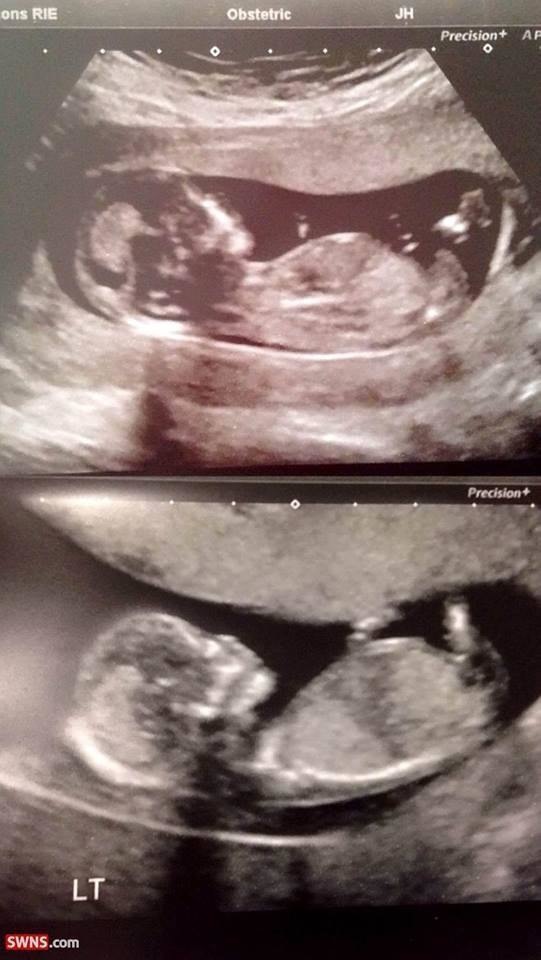

Two Special BoysAlanna war sehr glücklich, ihren Zwillingsjungen zur Welt zu bringen. Es war das wertvollste Gefühl, ihre Neugeborenen glücklich und gesund zu sehen. Glücklicherweise zeigten alle Scans, die die Ärzte der Babys taten, zeigten, dass sie in perfekter Größe und Gesundheit waren. Alanna hätte nicht mehr erwarten können.

Twin BoysIn der Gnade des Allmächtigen war Alanna wieder schwanger. Überraschenderweise erwarteten sie Zwillinge! Die Tatsache, dass sowohl Alanna als auch ihr Ehemann mit der Anwesenheit von vielen Zwillingen in ihrer Familie gesegnet waren, machten sie die Nachricht, dass Zwillinge sehr normal geboren wurden.

Smooth SailingOhne Gefahr zu nehmen, ging Alanna häufig für Check-ups. Shona Finch, der Manager für Mutterschaft bei NHS Lothian, sagte: "Zwillinge können oft kleiner sein, wenn sie geboren werden." Glücklicherweise leitete die Schwangerschaft von Alannas sehr gut. "Wir haben ihr Wachstum in der gesamten Schwangerschaft von Alannas überwacht, also wussten wir, dass sie beide gesunde Gewichte sein würden", sagte Finch.

Growing Big And StrongDie Scans zeigten die Tatsache, dass die Zwillinge größer als der Durchschnitt sein würden. "Die Scans sagten, dass sie gute Größen waren, und die Hebammen erzählten mir, dass sie gut gewachsen sind", sagte Alanna.Still, Alanna konnte die Spekulation nicht glauben, dass die Krankenschwestern nicht glauben konnte in Bezug auf die Größe ihrer Babys gemacht.

Image result for two very fat twins newbornMit einem kombinierten Gewicht von 16lb 13z, waren die Zwillinge die Größe eines sechs Monatsalters. "Das Personal des Krankenhauses sagte zu mir, dass sie noch nie Zwillinge zuvor gemacht haben", sagte Alanna. Es war sicherlich etwas, das nicht oft passiert. Alanna fühlte sich wie eine stolze Mutter an.

Record-Breaking BabiesDie Merrie-Zwillinge erwiesen sich als Rekordschalter. Als, bevor sie geboren wurden, waren die größten Zwillinge, die in Schottland geboren wurden, mya und Ollie Kennedy im Jahr 2010 mit einem kombinierten Gewicht von 15lb 14z. Ihre Rekord wurde von Troy und Kaius Merrie abgerissen. "Ein kombiniertes Gewicht von 16lb 13z ist sehr ungewöhnlich und wahrscheinlich der schwerste Set von Zwillingen, die wir je in Lothian geliefert haben", sagte Finch.